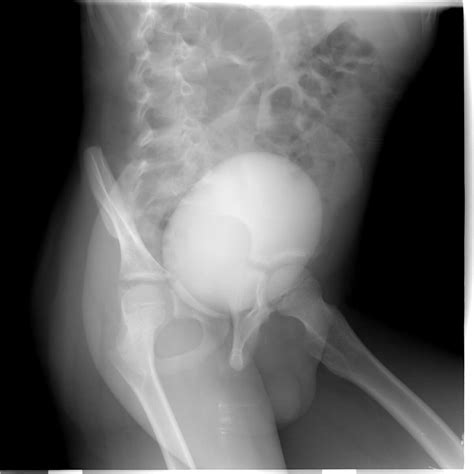

Voiding Cystourethrogram (VCUG) Uses contrast dye to see if the pouch fills during urination.

Diagnosis requires a high index of suspicion, especially when standard treatments for UTIs fail. A physician will typically perform a physical exam, which may reveal a tender mass along the anterior vaginal wall. If pressure is applied to the mass, it is not uncommon for a small amount of urine or purulent discharge to exit the urethra.